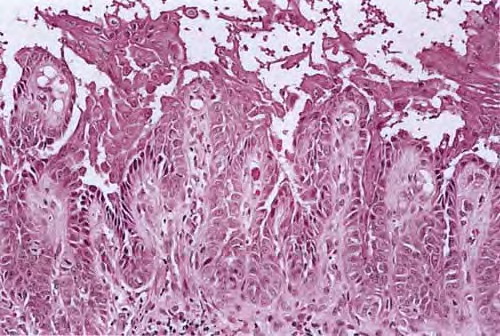

The center of the lesion is occupied by a large, cup-shaped invagination connected with the surface by a channel filled with keratinous material . The large invagination contains numerous acantholytic, dyskeratotic cells in its upper portion. The lower portion of the invagination is occupied by numerous villi, that is, markedly elongated dermal papillae that are often lined with only a single layer of basal cells and project upward from the base of the cup-shaped invagination  . Typical corps ronds can I

usually be seen in the thickened granular layer lining the channel at the entrance to the invagination .